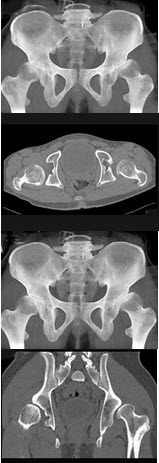

88、单项选择题

女,60岁,髋部疼痛、活动受限、跛行,结合图像,最可能的诊断是()

A.骨岛

B.髋关节结核

C.股骨头缺血坏死

D.退变性囊肿

E.暂时性骨质疏松

点击查看答案

127、单项选择题

男,23岁,跛行,外展受限,两下肢不等长,结合图像,最可能的诊断是()

A.髋关节中心脱位

B.髋关节后脱位

C.髋关节前脱位

D.先天性髋内翻

E.髋关节结核

150、单项选择题

女,根据其正常骨盆影像图像,判断其最可能的年龄()

A.28岁左右

B.18岁左右

C.38岁左右

D.78岁左右

E.58岁左右